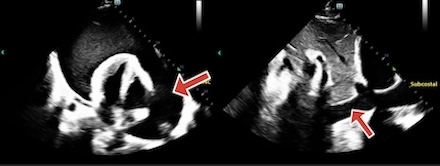

A 44 year old male with ESRD on intermittent hemodialysis (iHD) presented with chest pain and systolic blood pressure in the 80s. Exam showed jugular venous distension. Transthoracic echocardiogram revealed a large pericardial effusion without tamponade (Figure A). Pericardiocentesis drained 2.5 liters of sanguineous fluid (Figure B). Post procedure, the patient's mean arterial pressure decreased beneath 65 mmHg. Bedside echocardiogram was concerning for right ventricular dilation. The drain was temporarily clamped, and the patient received vasopressors. He underwent continuous renal replacement therapy (CRRT) for fluid optimization before returning to iHD with improved ultrafiltration goals. By day seven, the drain produced less than 50 mL of fluid over the previous twenty-four hours. Bedside echocardiogram was confirmatory, so the drain was removed. The patient was discharged with outpatient cardiology follow-up.

Despite the large effusion, the absence of tamponade suggests chronic fluid accumulation, allowing gradual pericardial stretch, reduced intra-pericardial pressure change, and hemodynamic compensation. In this patient, pericardial decompression syndrome occurred from suddenly increased venous return, rapid right sided expansion (as shown on bedside echocardiogram), septal shift, left ventricular compression, decreased output, and ultimately hypotension. Another factor may have been the sudden change in preload with relatively unchanged systemic vascular resistance, thus preload/afterload mismatch. The effusion was likely due to insufficient fluid removal during dialysis, emphasizing the importance of dialysis quality in preventing cardiac complications. However, decompression syndrome is rare, with less than 5% incidence among patients who undergo drainage.